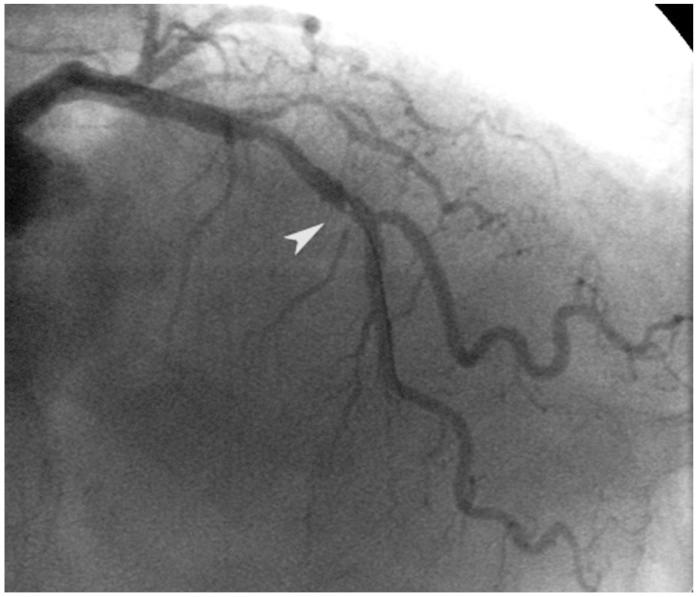

Although its use in daily practice is not common, optical coherence tomography (OCT) is a powerful research tool in invasive cardiology. This report describes a hazy angiography image after percutaneous coronary intervention that has been assessed using OCT. Based on the results of the OCT, the patient underwent an elective coronary angioplasty with standard anticoagulation. After implantation of the stent, an intracoronary hazy image was seen on angiography. The use of OCT permitted a correct diagnosis and a successful treatment. This paper provides a discussion of the advantages and disadvantages of OCT, and a comparison with intravascular ultrasound.

虽然在日常实践中并不常用,但光学相干断层扫描(OCT)是介入心脏病学中强有力的研究工具。本报告描述了经皮冠状动脉介入治疗后使用 OCT 评估的模糊血管造影图像。根据 OCT 的结果,患者接受了标准抗凝的选择性冠状动脉血管成形术。支架植入后,血管造影显示冠状动脉内出现模糊图像。OCT 的使用可以明确诊断并成功治疗。本文讨论了 OCT 的优缺点,并与血管内超声进行了比较。